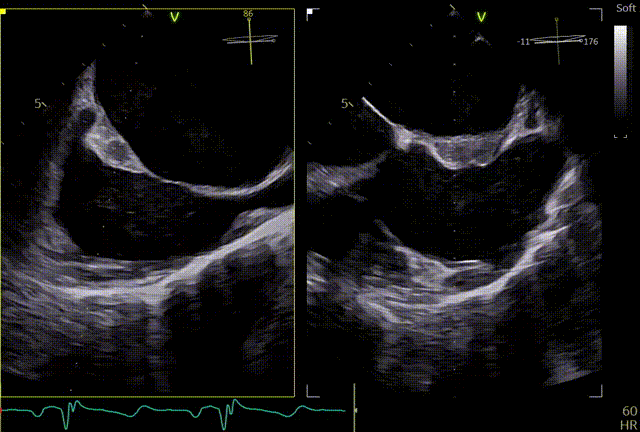

术前TEE及左房压

1区

1区带彩

2区

2区带彩

3区

3区带彩

3D

3D带彩

术前肺静脉频谱

3区gap

术前左房压